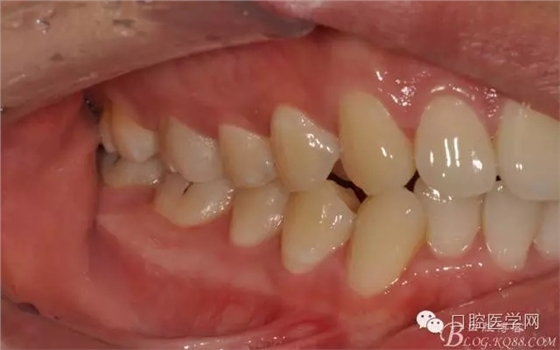

檢查:16近中齲壞深,探痛,已露髓,冷測痛明顯,叩痛(+-),無松動全口牙石(++),牙齦紅腫。

圖3 牙體預(yù)備前頜面觀

圖4 牙體預(yù)備前咬頜觀